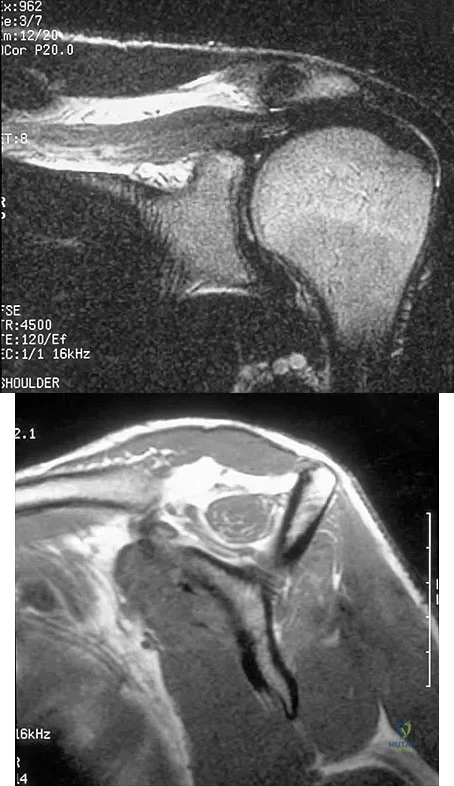

Figures 36a and 36b show the MRI scans of a patient who has shoulder weakness. What is the most likely diagnosis?

Explanation